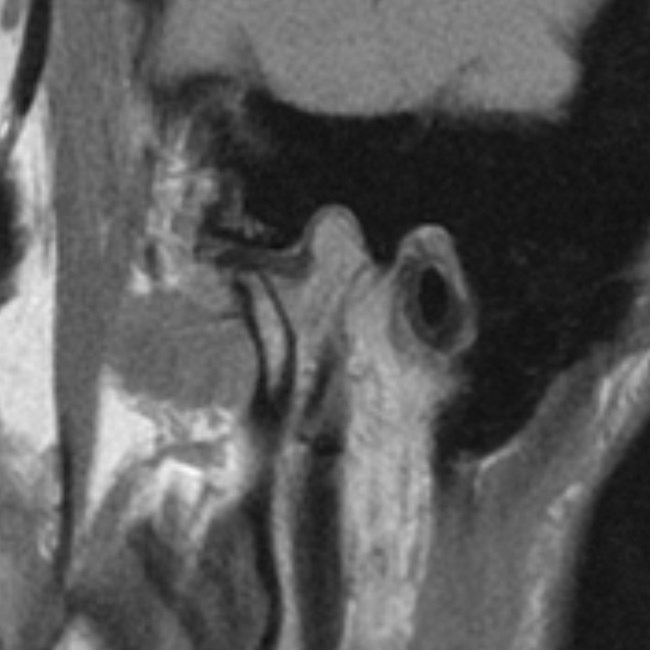

Na podstawie uzyskanych wyników badań zastosowano repozycyjną szynę zgryzową oraz terapię manualną narządu żucia. Po trzymiesięcznym leczeniu uzyskano poprawę modelu ruchomości żuchwy. W związku z utrzymywaniem się silnych dolegliwości bólowych zlecono dodatkowo badanie tomografii rezonansu magnetycznego (MR), w którym w zwarciu stwierdzono obustronne doprzednie przemieszczenie krążków stawowych (ryc. 5). W zwarciu na przekrojach czołowych widoczne było spłaszczenie powierzchni stawowej lewego ssż (ryc. 6). W rozwarciu pozycja obydwu głów żuchwy była doprzednia w stosunku do szczytów guzków stawowych, a nad głowami żuchwy leżały pasma przednie krążków stawowych. Przemieszczenie głowy żuchwy było bardziej nasilone w prawym stawie skroniowo-żuchwowym (ryc. 7).

Ryc. 7a i 7b. Przekroje strzałkowe MR ssż w rozwarciu, obrazy PD-zależne. Doprzednie położenie głów żuchwy w obydwu ssż, nad głowami żuchwy widoczne pasma przednie krążków stawowych.